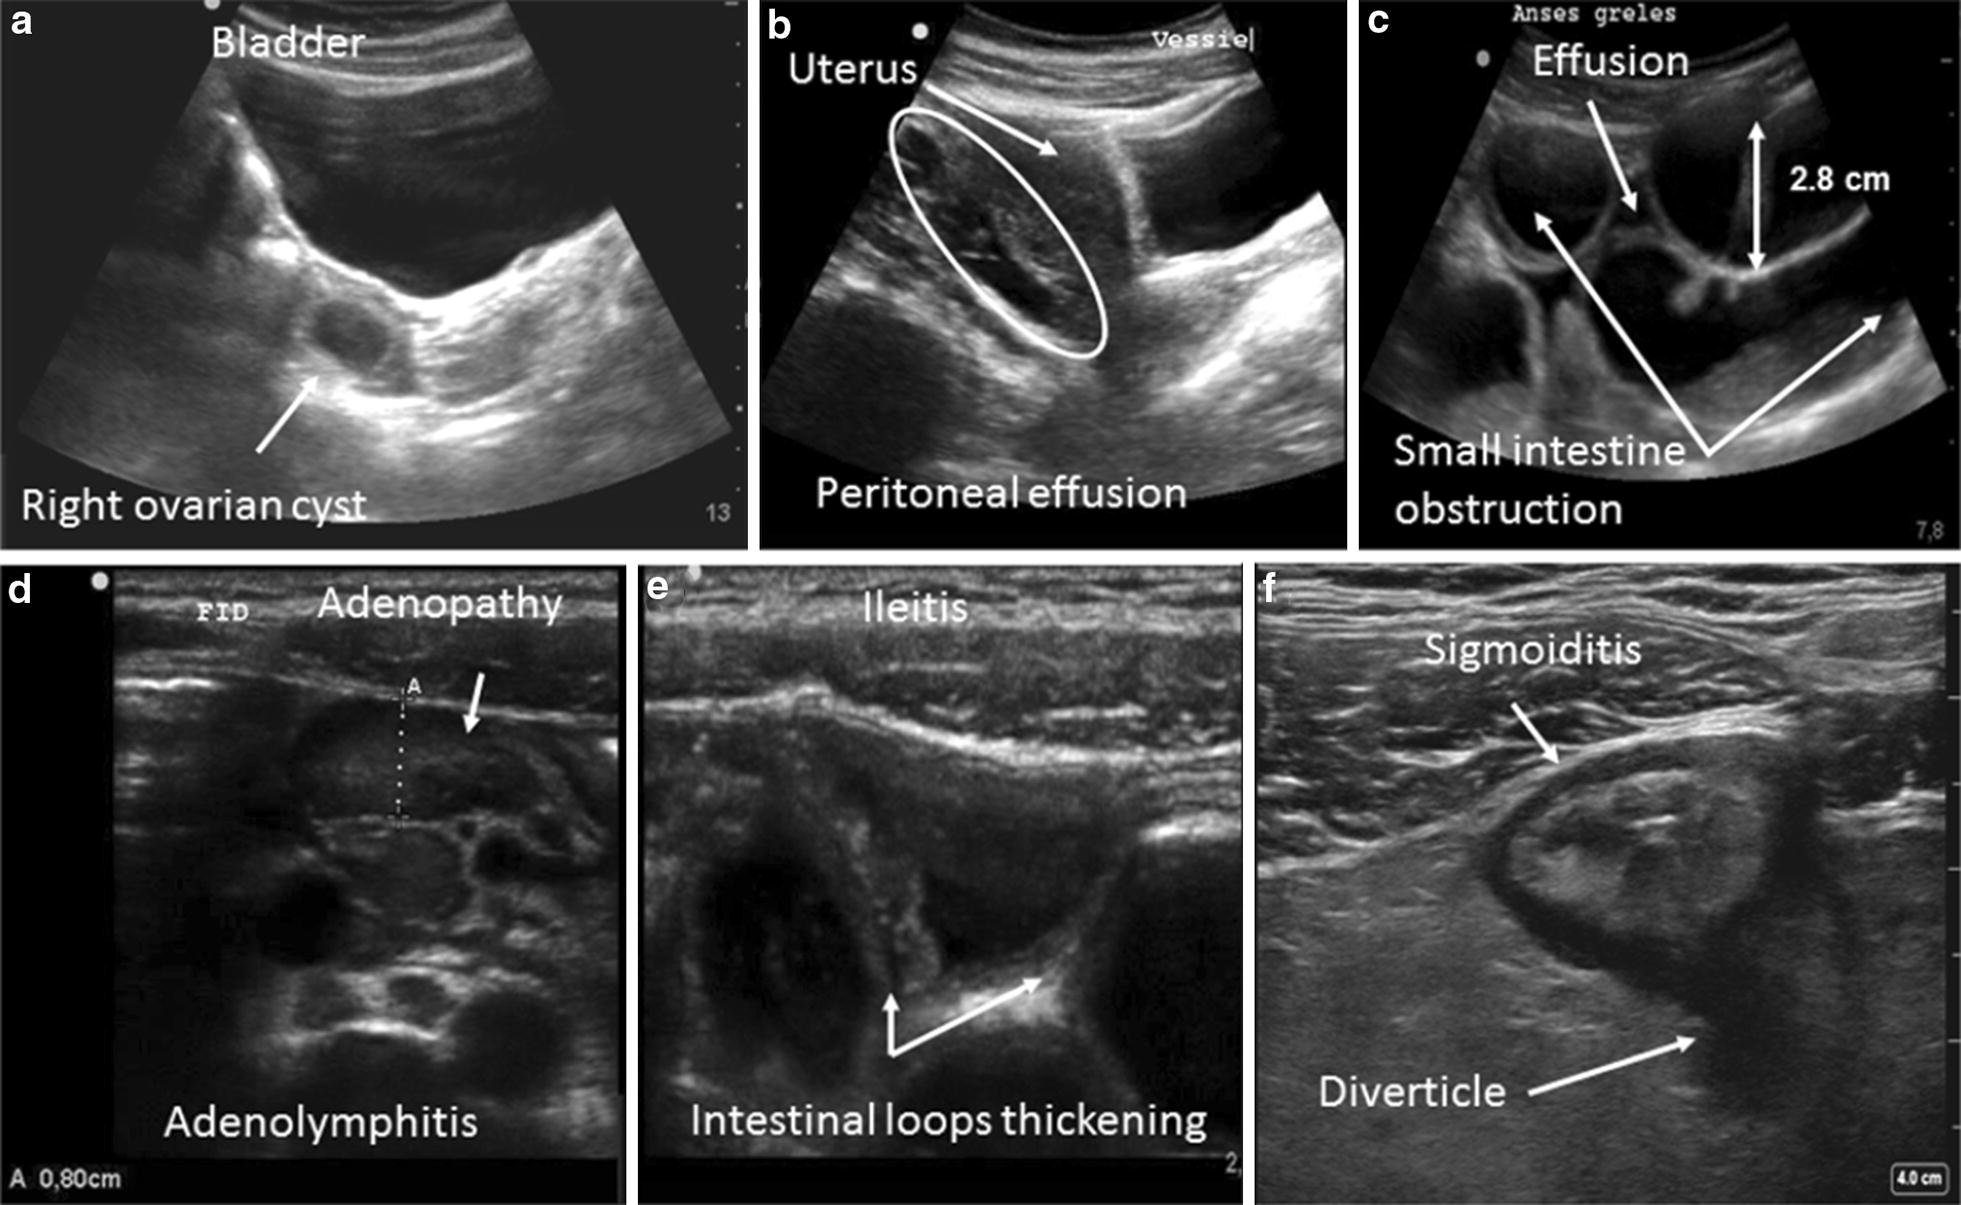

Other pathological images can also be seen, such as an intra-peritoneal effusion, an obstruction syndrome, inflammatory adenopathies, and complicated ovarian cyst [25–27] (Fig. 1).

Fig. 1.

Examples of abnormal ultrasound images: a a latero-uterine mass with a sonolucent liquid content suggestive of a complicated ovarian cyst, b isolated peritoneal effusion (often at the bottom of the Douglas pouch), c appearance of a small intestinal occlusion (widening of the intestinal loops by more than 2.5 cm, with a liquid content and possible inter-loop effusion), d adenopathies (hypoechoic oval images greater than 5 mm in terms of the antero-posterior diameter, sensitive to passage of the probe, and enhanced by color Doppler), e thickening of the last small intestinal loops suggestive of ileitis (thickening by more than 3 mm of the wall of the digestive tract), f circumferential widening of the colon wall (a pseudo-kidney appearance) suggestive of an inflammation or an infection